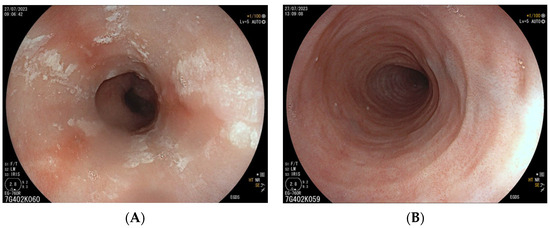

7.2. Eosinophilic Esophagitis